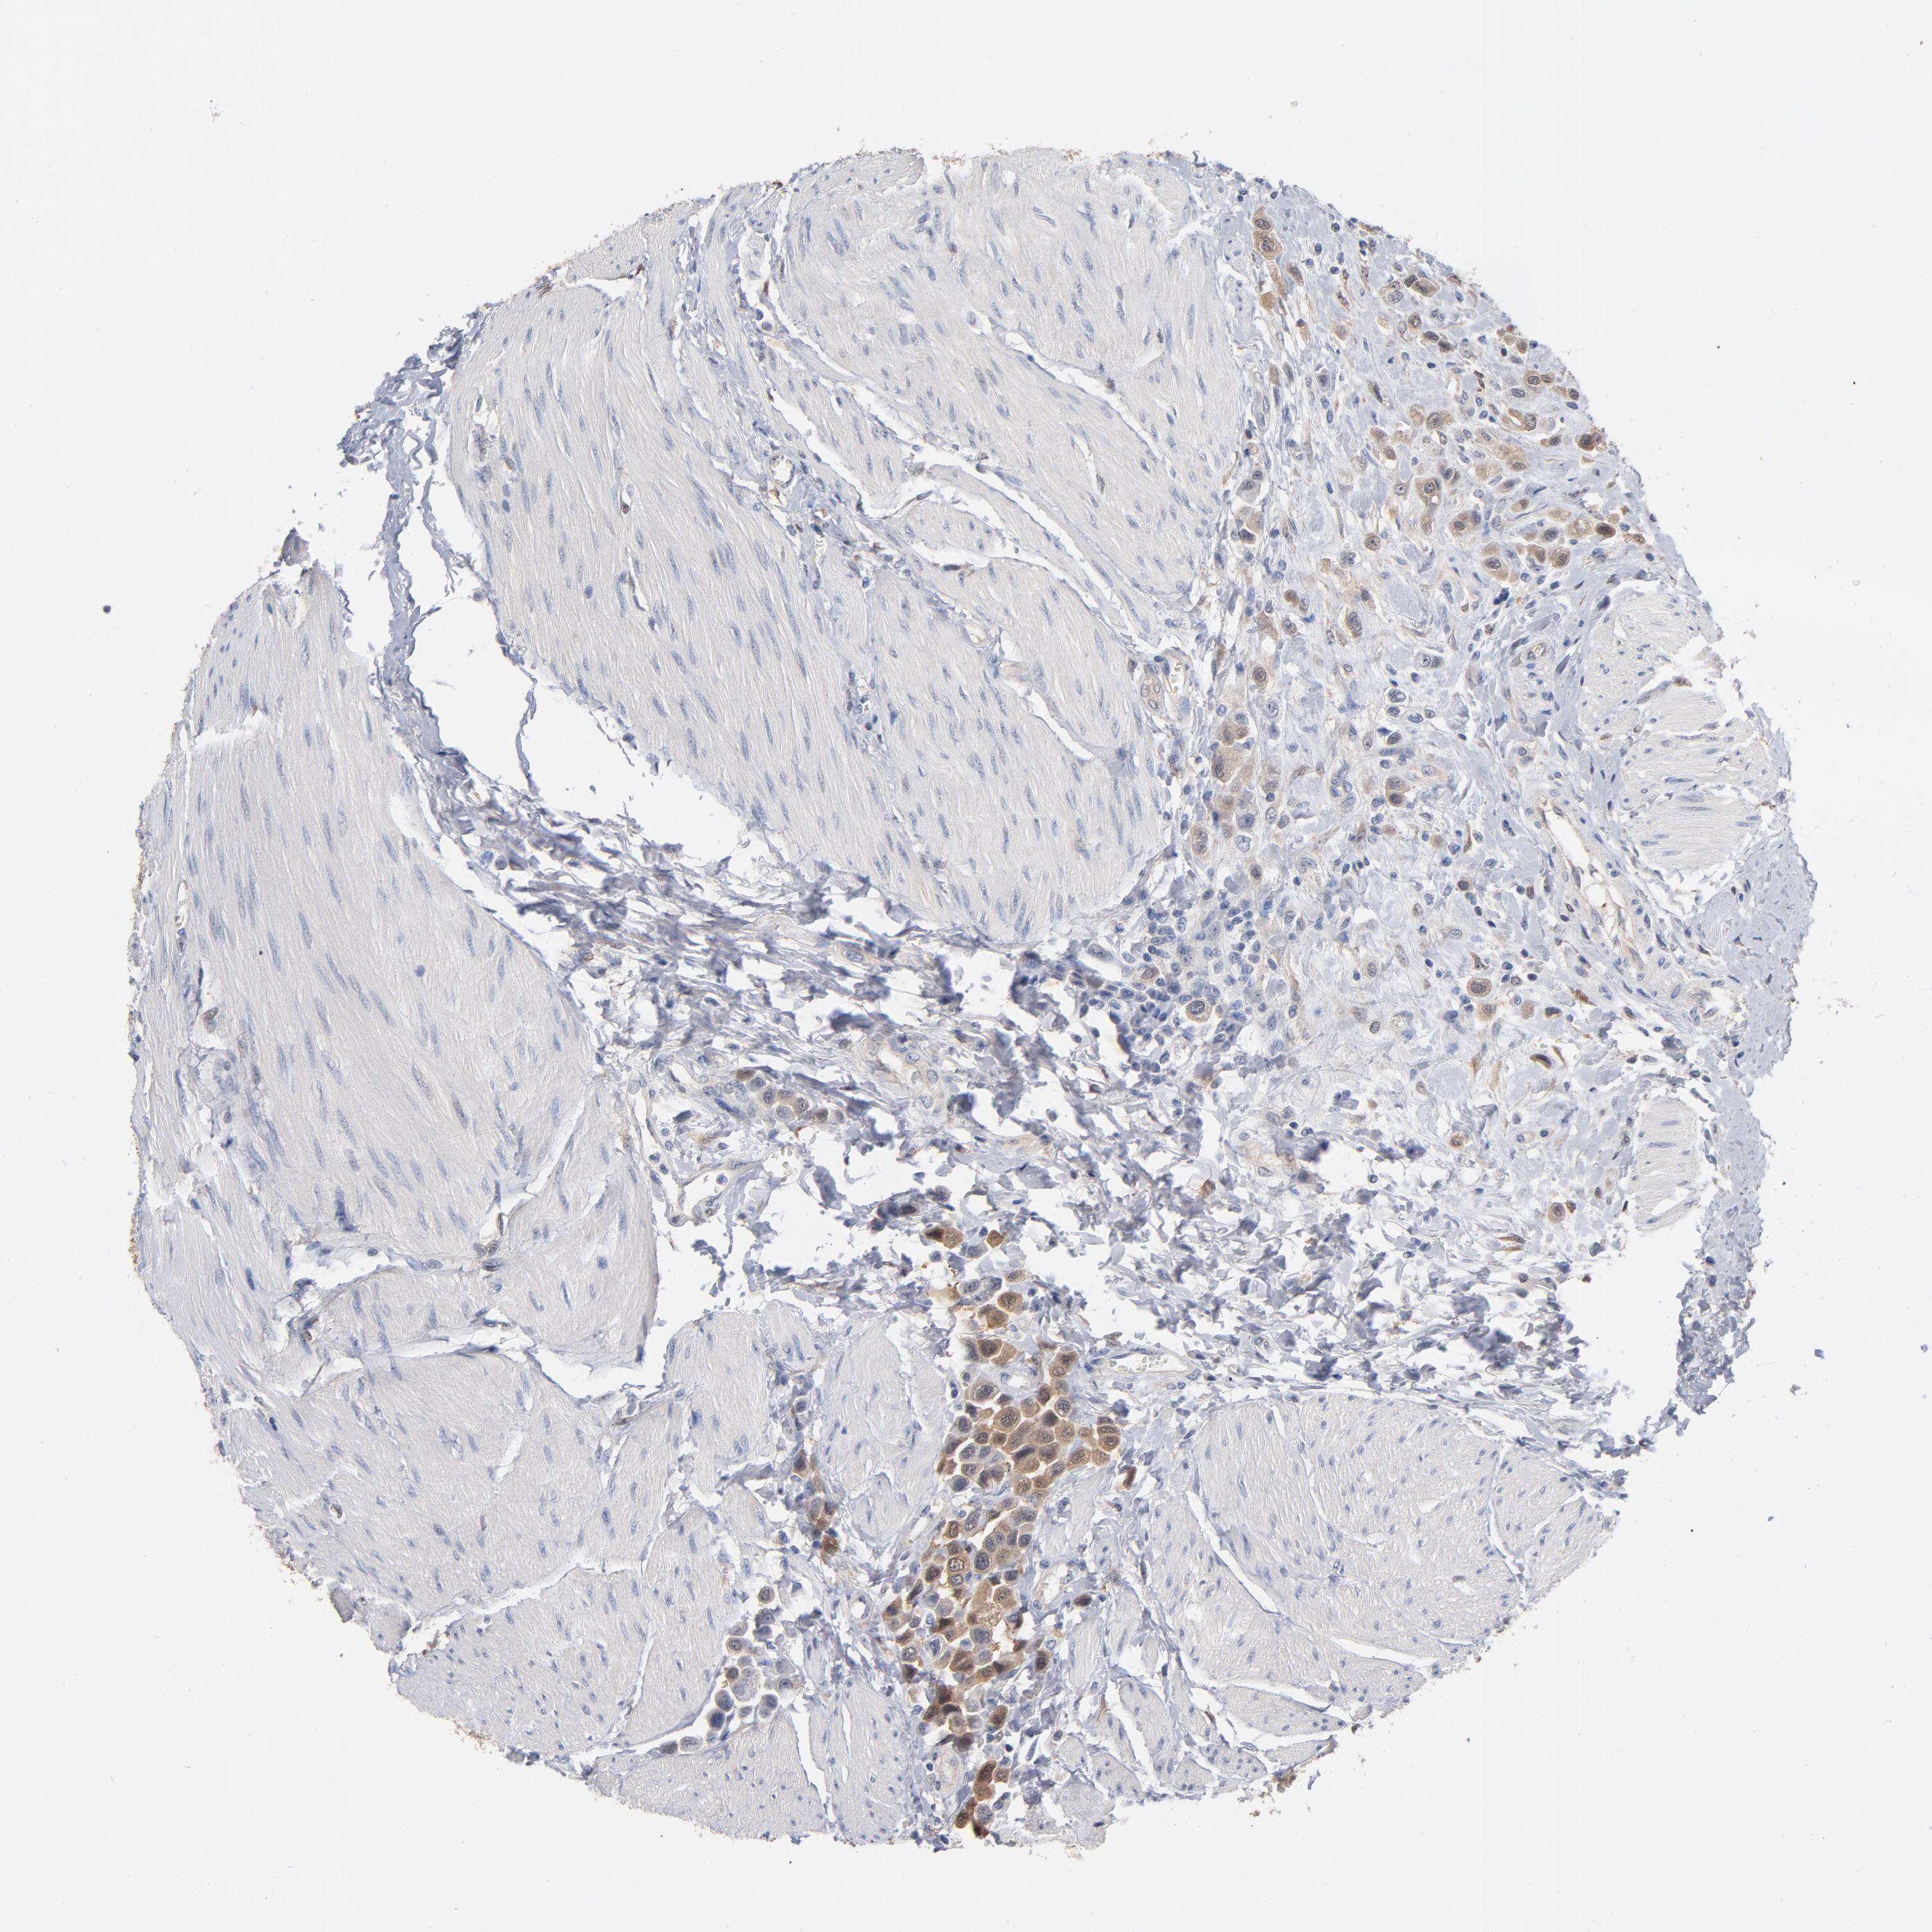

UROTHELIAL CANCER - Protein expressioni

A mouse-over function shows sample information and annotation data. Click on an image to view it in a full screen mode. Samples can be filtered based on level of antibody staining by selecting one or several of the following categories: high, medium, low and not detected. The assay and annotation is described here.

Note that samples used for immunohistochemistry by the Human Protein Atlas do not correspond to samples in the TCGA dataset.

Antibody stainingi

Antibody staining in the annotated cell types in the current human tissue is reported as not detected, low, medium, or high, based on conventional immunohistochemistry profiling in selected tissues. This score is based on the combination of the staining intensity and fraction of stained cells.

Each image is clickable and will lead to virtual microscopy that enables deeper exploration of all samples and also displays staining intensity scores, fraction scores and subcellular localization as well as patient and tissue information for each sample.

Antibody HPA003868

Antibody CAB005284

Staining

High

Medium

Low

Not detected

Intensity

Strong

Moderate

Weak

Negative

Quantity

>75%

75%-25%

<25%

None

Location

Nuclear

Cytoplasmic/membranous

Cytoplasmic/membranous,nuclear

Urothelial carcinoma, High grade

Urothelial carcinoma, Low grade